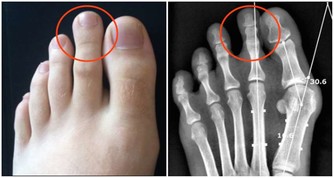

牙科的x光片可以作為骨質疏鬆症的篩查工具,

研究表明牙科x光片與正常骨密度的人相比,可以鑑別是否患有骨質疏鬆症。